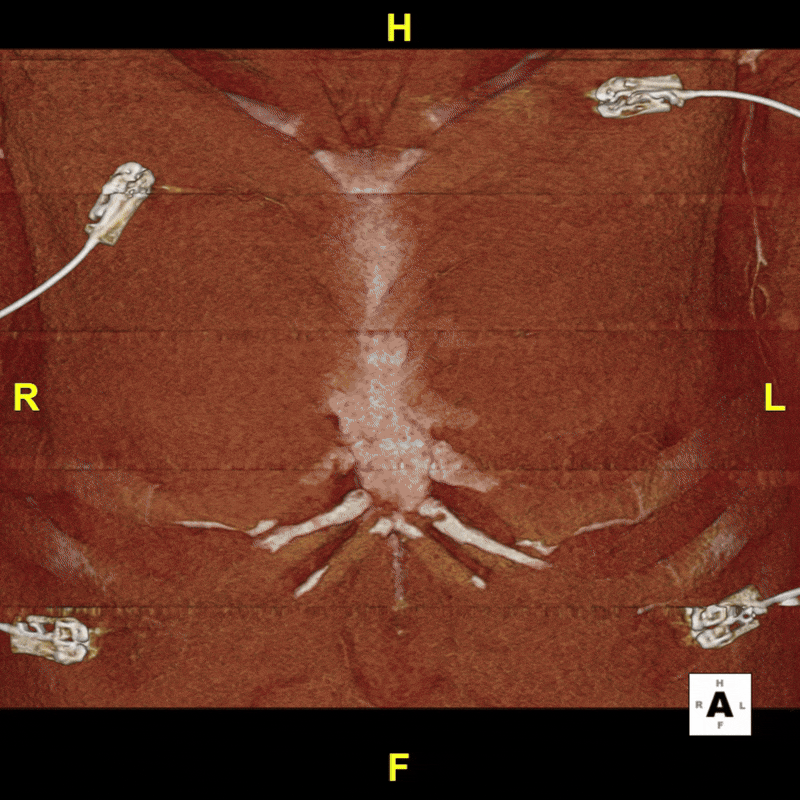

Figure A (Right): 4D rotational volume render of the heart and thoracic aorta, showing the arch branching pattern, Kommerell diverticulum, and proximal descending aneurysm. (Learn more about 4D/ time resolved imaging here).

Figure G: Targeted volume renderings of the heart, thoracic aorta, and coronary arteries for visualization of anatomy and vessel morphology. (Learn more about volume renders here).